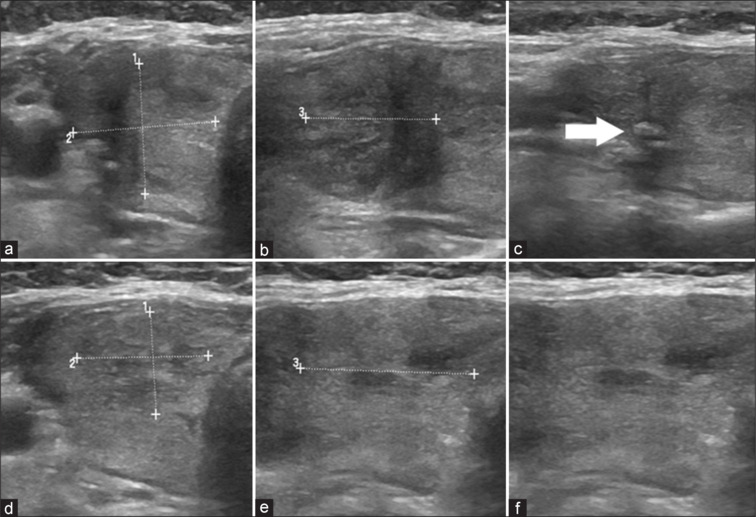

A 48-year-old female, a known case of ulcerative colitis, on routine workup, was incidentally detected to have biochemical hyperthyroidism. 99mTc pertechnetate thyroid scintigraphy performed for the evaluation of hyperthyroidism revealed two foci of increased tracer uptake in the right thyroid lobe with suppressed uptake in the rest of the thyroid gland consistent with dual autonomously functioning thyroid nodules.

一位48岁女性,已知溃疡性结肠炎病例,在常规检查中偶然发现生化甲状腺功能亢进。用于评估甲亢的99mTc高技术甲状腺显像显示,右侧甲状腺叶有两个示踪剂摄取增加的病灶,而甲状腺其余部分的摄取受到抑制,与双重自主功能甲状腺结节一致。